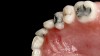

(12. and 13.) Intraoral photographs taken with a smartphone and an EALS device for orthodontic evaluation.

Figure 12

Figure 13